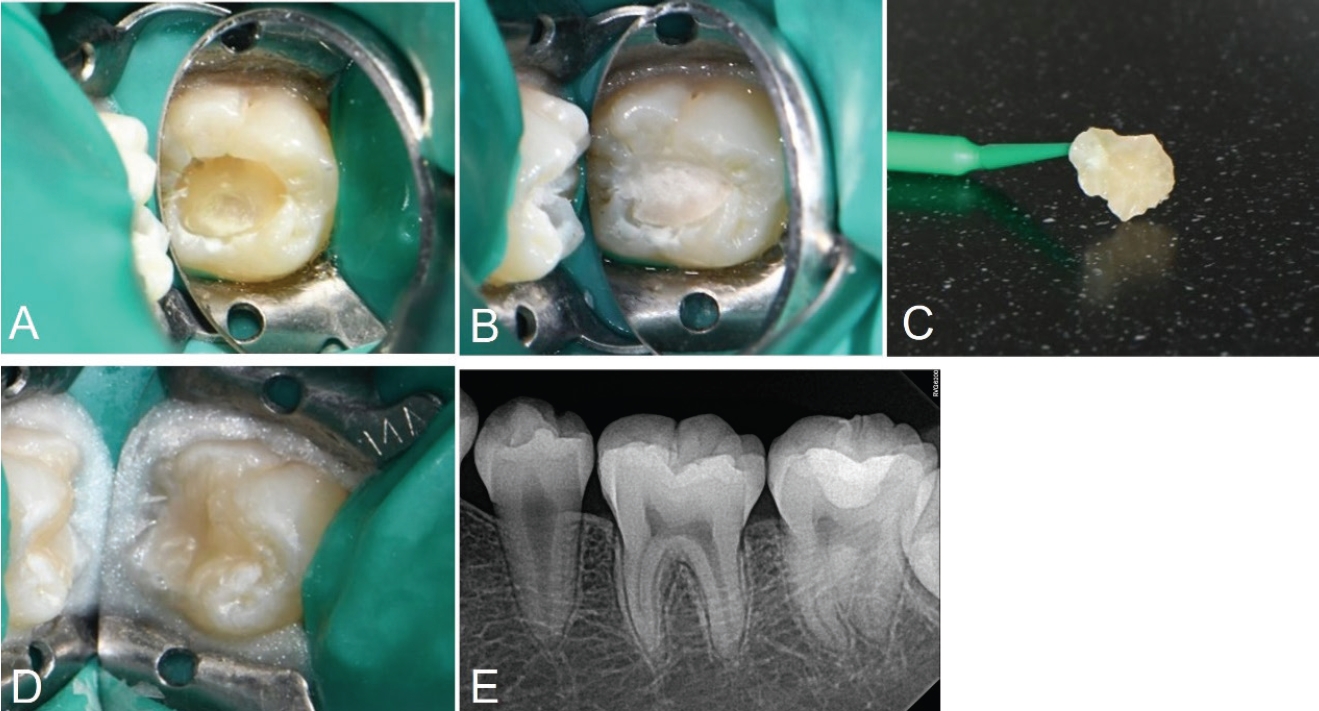

13세 여성 환자가 부산대학교치과병원 치과보존과에 좌측 하악 구치부 우식을 주소로 내원하였다. 환자의 전신 병력 및 치과 병력 특이사항은 없었다. 구내 검사에서는 좌측 하악 제2대구치에서 치면열구 우식이 관찰되었다. 교합면 형태는 보존되어 있었고, 명확한 공동(cavitation)은 관찰되지 않았다(Fig. 3A). 원심 및 설측 교합면 일부가 미맹출하여 치은판개에 덮여 있었다. 냉자극과 온자극에 대한 반응은 정상적이었다. 타진이나 저작에 대한 통증도 없었다. 파노라마 및 구내 치근단 방사선사진 상 상아질까지 진행된 깊은 우식을 관찰할 수 있었다(Figs. 3B and C). 이 결과를 바탕으로 우식 부위를 복합레진으로 수복하면서 스탬프 테크닉을 적용하기로 결정하였다.

Fig. 3.

Initial examination radiograph and clinical photograph. A. No loss of tooth structure was observed. B. Preoperative panoramic radiograph. C. Caries of dentin is seen on olwer left second molar.